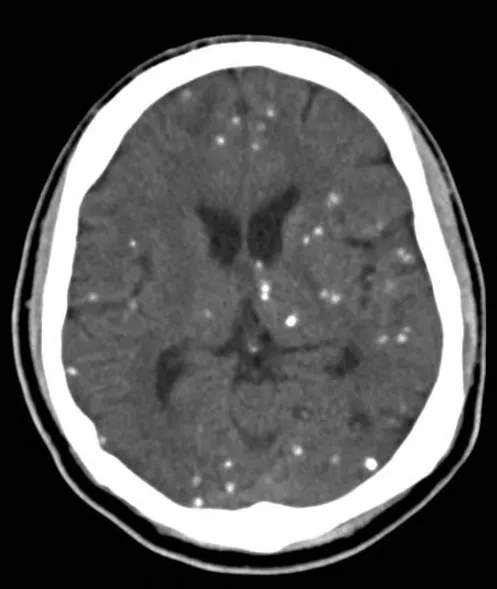

(2) Cysticercosis

① Larval form of pork tape worm, Taenia solium

② 모든 tissue에서 발견되며 CNS 침범 시 neurocysticercosis라 한다.

③ 양상 : 1st seizure, obstructive hydrocephalus, stroke, headache, mental change

④ 진단 : Noncontrast CT (calcification, hydrocephalus 확인 가능)

⑤ 치료 : Praziquantel 50mg/kg/d PO 15일간 or albendazole

Steroid (뇌염,수막염,혈관염 피하기 위해)

•

Cysticercosis의 특징적인 brain CT finding(multiple calcification)